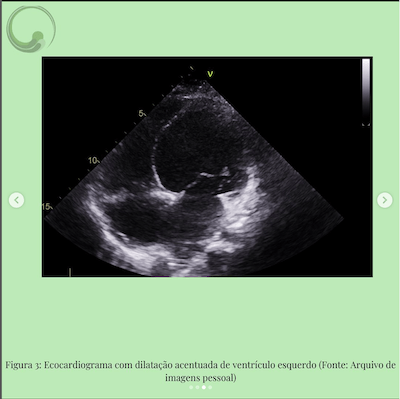

GI 5 anos, portadora de miocardiopatia dilatada sem causa definida, último ECO há 5 meses com FEVE 25%o, em uso de captopril zmg/kg/dia, carvedilol 0,3mg/kg/dia, furosemida 2 mg/kg/dia e espironolactona img/kg/dia. Paciente dá entrada no pronto socorro com quadro de febre há 2 dias, desconforto respiratório e tosse, mãe refere inapetência, prostração e redução da diurese hoje.